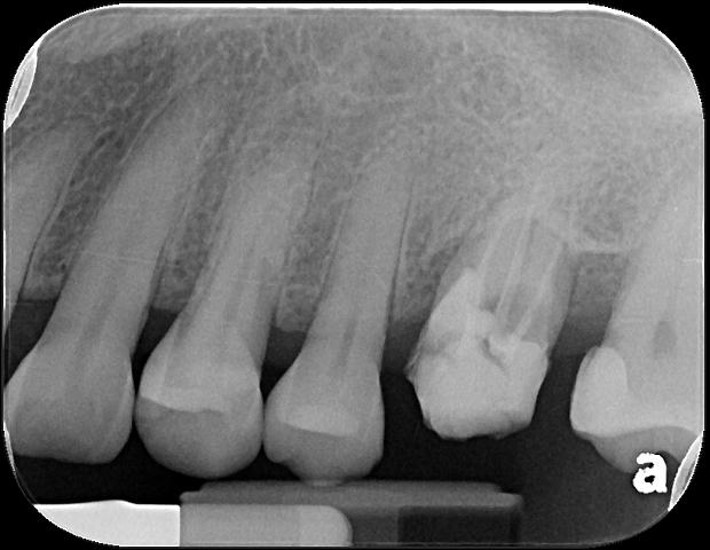

治療前,根管後大臼齒有牙裂

治療前,根管後第一大臼齒有牙裂

治療前,根管後大臼齒根部有蛀牙裂